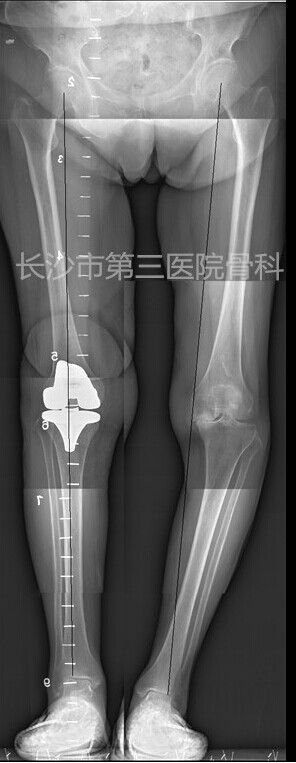

术前下肢全长片:

术后影像学资料: